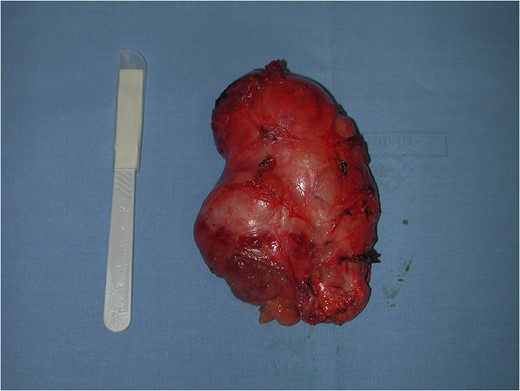

Surgical treatment was carried out with a posterior approach (Fig. 5). The lesion was in close proximity of elevator ani muscle and lateral rectal wall, that were not macroscopically infiltrated. The lesion area was marked with surgical clips because of the close proximity with rectal wall, for eventual post-operative chemotherapy or radiotherapy and for follow-up. Surgical specimen was an oval, soft tissue mass of 11 × 7.5 × 5.5 cm in size, capsulated, hyper-vascularized, with a inhomogeneous aspect, multi-lobed (Fig. 6). Microscopically, the tumour was composed by a proliferation of spindle cells crossed by stromal collagen and giant plurinucleate cells. Neoplastic cells immunophenotype showed expression for CD34 and bcl-2 (Figs 7–9).

Posterior surgical approach and intra-operatory appearance of the neoplasm.